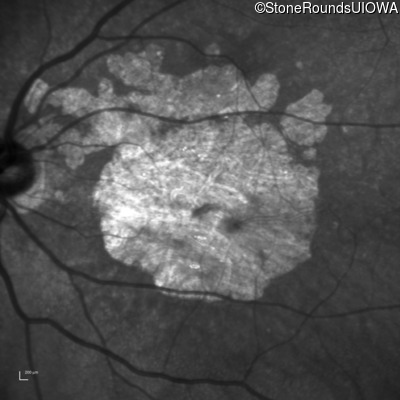

Blue Autofluorescence - Left - 10/200

Exemplar